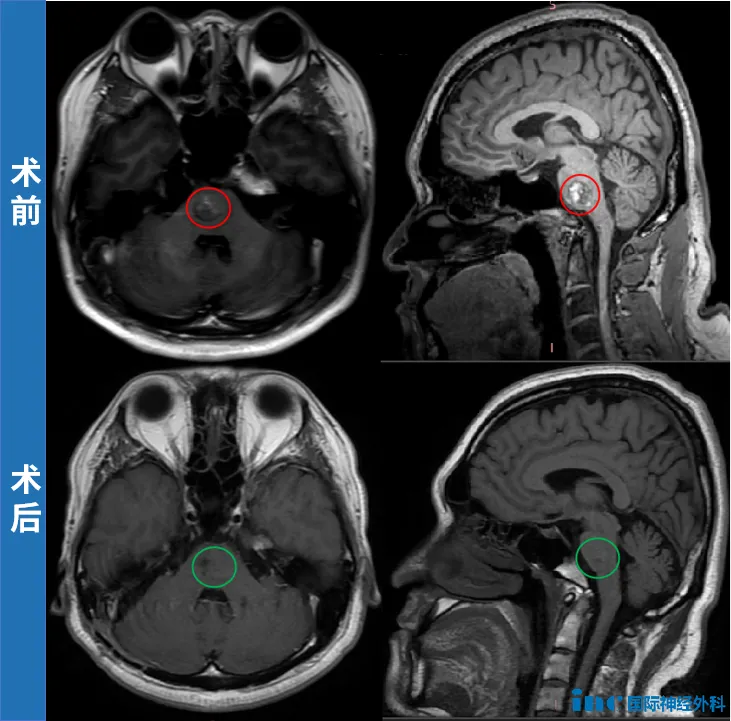

提到脑干手术,很多人会想到手术禁区这个词。尤其是中脑海绵状血管瘤,这类位于脑干核心区域的病变,过去常被认为越深越危险,甚至被排除在手术选项外。 INC国际脑干手术大咖Helmut Ber...